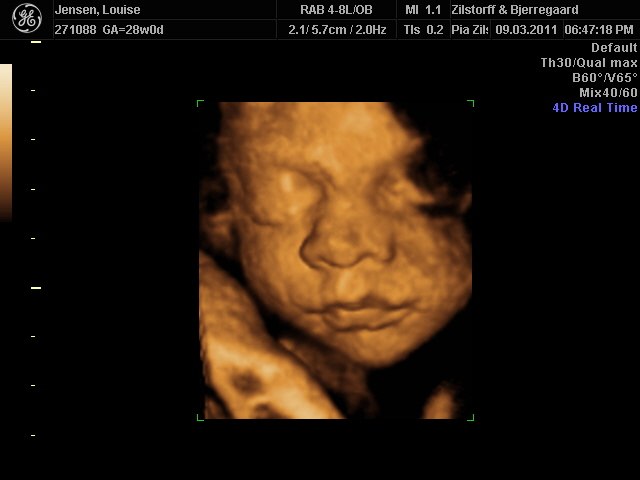

Jeg og kæresten var til 3D-scanning igår - sikke da en oplevelse  - det er da helt klart alle pengene værd ..

Hold da op en smækker lækker baby'boy der gemmer sig derinde i hulen, fy føj mor her fik tårere i øjne .. sikke da alt den kærliighed der væltede over mig .. suk suk

han ligner han far meget  - det er så vidunderligt hvad man dog kan se..

perfekt hjertelyd og vægten siger 1166 og er i uge 29 nu

Vedhæftede fotos (klik for at se i fuld størrelse)